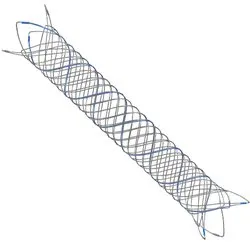

LVIS™ & LVIS™ Jr

Coil Assist Stents